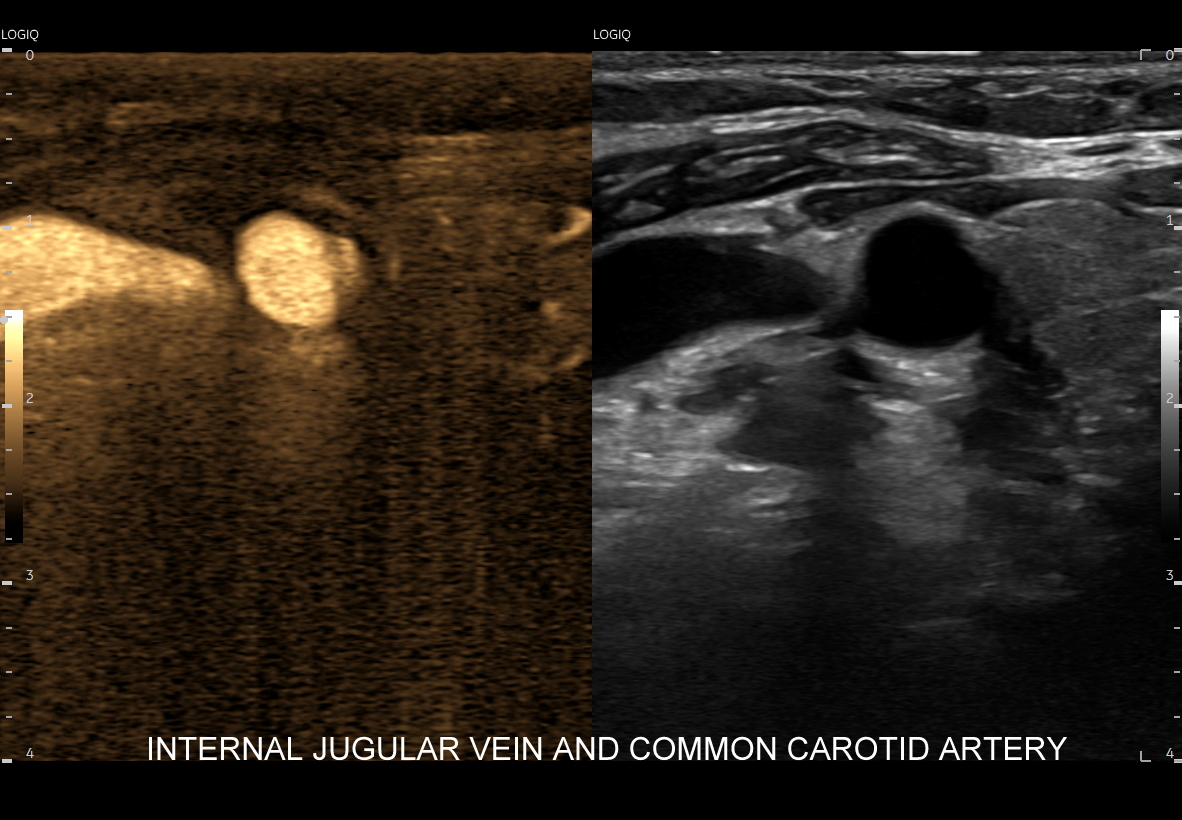

Tryb B-flow wyjątkowo korzystnie sprawdza się także przy badaniu wnętrza dużych i średnich naczyń. Otóż umożliwia on pewne zobrazowanie drożności naczynia, umożliwia wykazanie obecności / lokalizacji naczynia przy niesprzyjających warunkach obrazowania w trybie B, a poza tym uzyskiwane w omawianym trybie obrazy zarysów błony wewnętrznej naczyń (np. tętniczych blaszek miażdżycowych, skrzeplin przyściennych, zmian w przebiegu dysplazji włóknisto-mięśniowej, czy zapaleń tętnic) charakteryzują się wysoką rozdzielczością i kontrastowością. Skany dużych naczyń w trybie B-flow przypominają wręcz te uzyskiwane w klasycznej angiografii opartej o promieniowanie rentgenowskie. B-flow wykorzystywany może być praktycznie i rutynowo do obrazowania naczyń szyi i kończyn, naczyń wątroby, naczyń trzewnych, nerkowych oraz dużych naczyń brzusznych.